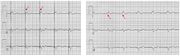

| 03:46, 6 August 2012 | ECGT.jpg (file) |  |

57 KB | 1 | |

| 04:41, 6 August 2012 | AtrialCap.jpg (file) |  |

75 KB | 1 | |